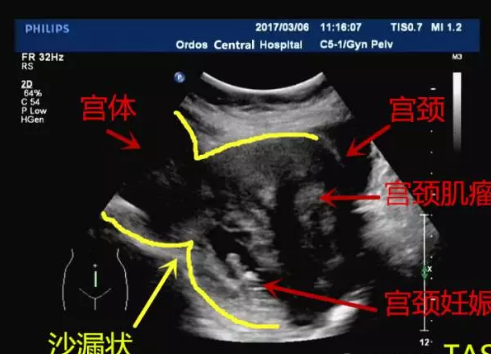

宮頸妊娠

宮頸妊娠是懷孕女性容易碰到的疾病問題,那么有關宮頸妊娠的疾病怎么治療,宮頸妊娠對胎寶寶的影響大嗎,下面八寶網就帶來專題介紹:宮頸妊娠。..